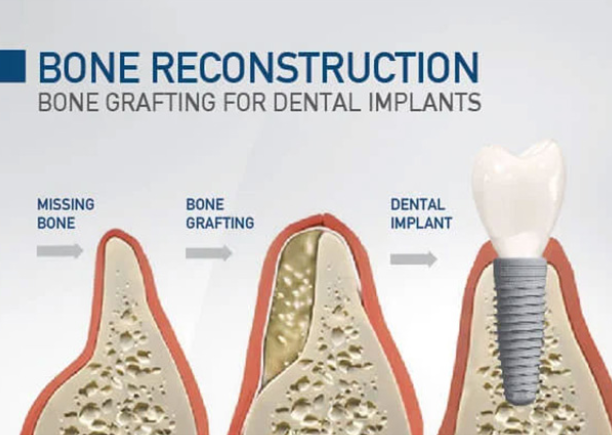

زراعة العظام

بناء الأساس لزراعة ناجحة

إجراءات متقدمة لتعزيز العظام واستعادة الحجم المفقود وتهيئة الظروف المثالية لوضع زرعات الأسنان.

تعزيز حافة الفك

إعادة بناء عرض عظم الفك لدعم الزرعات

حفظ التجويف

الحفاظ على حجم العظم بعد خلع السن

طعوم عظمية

زراعة كتل عظمية للعيوب الكبيرة

تجديد موجّه

نمو عظمي بمساعدة الأغشية لنتائج دقيقة